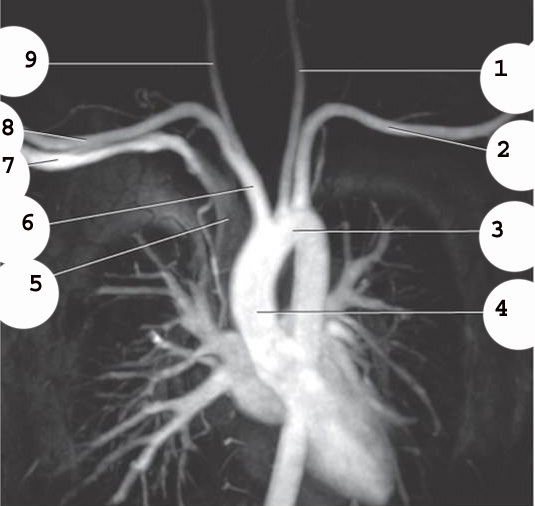

1

Rt brachiocephalic vein

2

brachiocephalic artery

3

L brachiocephalic Vein

4

L common carotid A

5

L subclavian artery

6

trachea

5 on the left

esophagus (there are 2 number 5’s)